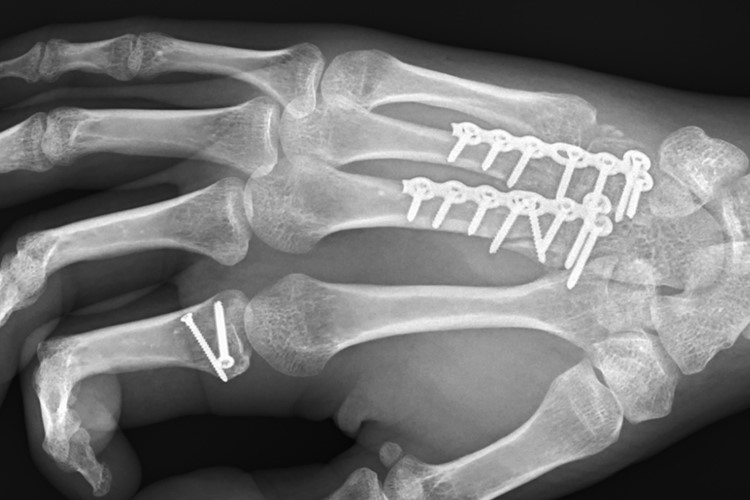

Wie im vorigen Jahr konnte ich den Schweizermeistertitel in der Superbike auch 2019 einfahren. Dabei begann die Saison 2019 denkbar ungünstig für mich. Ich hatte mich im Frühjahr in Spanien bei einem Trainingssturz relativ schwer verletzt. In meiner rechten Gashand stecken jetzt noch 18 Schrauben, 2 Platten, aber ich darf im späten Oktober mich vom Metall endlich befreien lassen. Die Verletzung hat mir mehr zu schaffen gemacht als ich zuerst wahr haben wollte. Ein Rennfahrer will immer sofort wieder aufs Motorrad. So richtig ohne allzu viel Schmerzen ging es aber erst nach der Saisonhälfte.